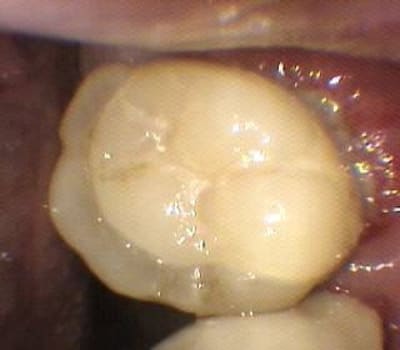

pour répondre à la question initiale du post, un cas de molaire dépulpée non couronnée.

Mise en place d'un cvimar (fuji II lc) en recouvrement de l'entrée canalaire puis onlay Empress collé.

Patiente de 21 ans.